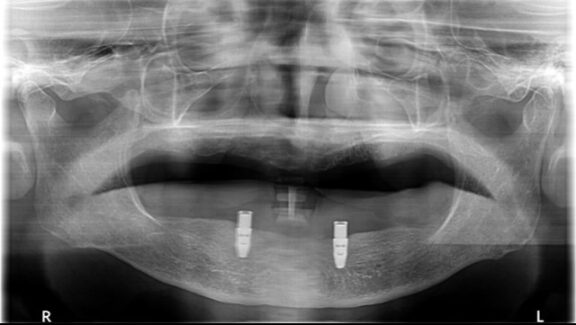

※インプラント埋入後のレントゲンです。

※インプラント(人工歯根)に

固定装置(ロケーターアバットメント)を取り付け、

義歯にも固定装置を取り付けました。